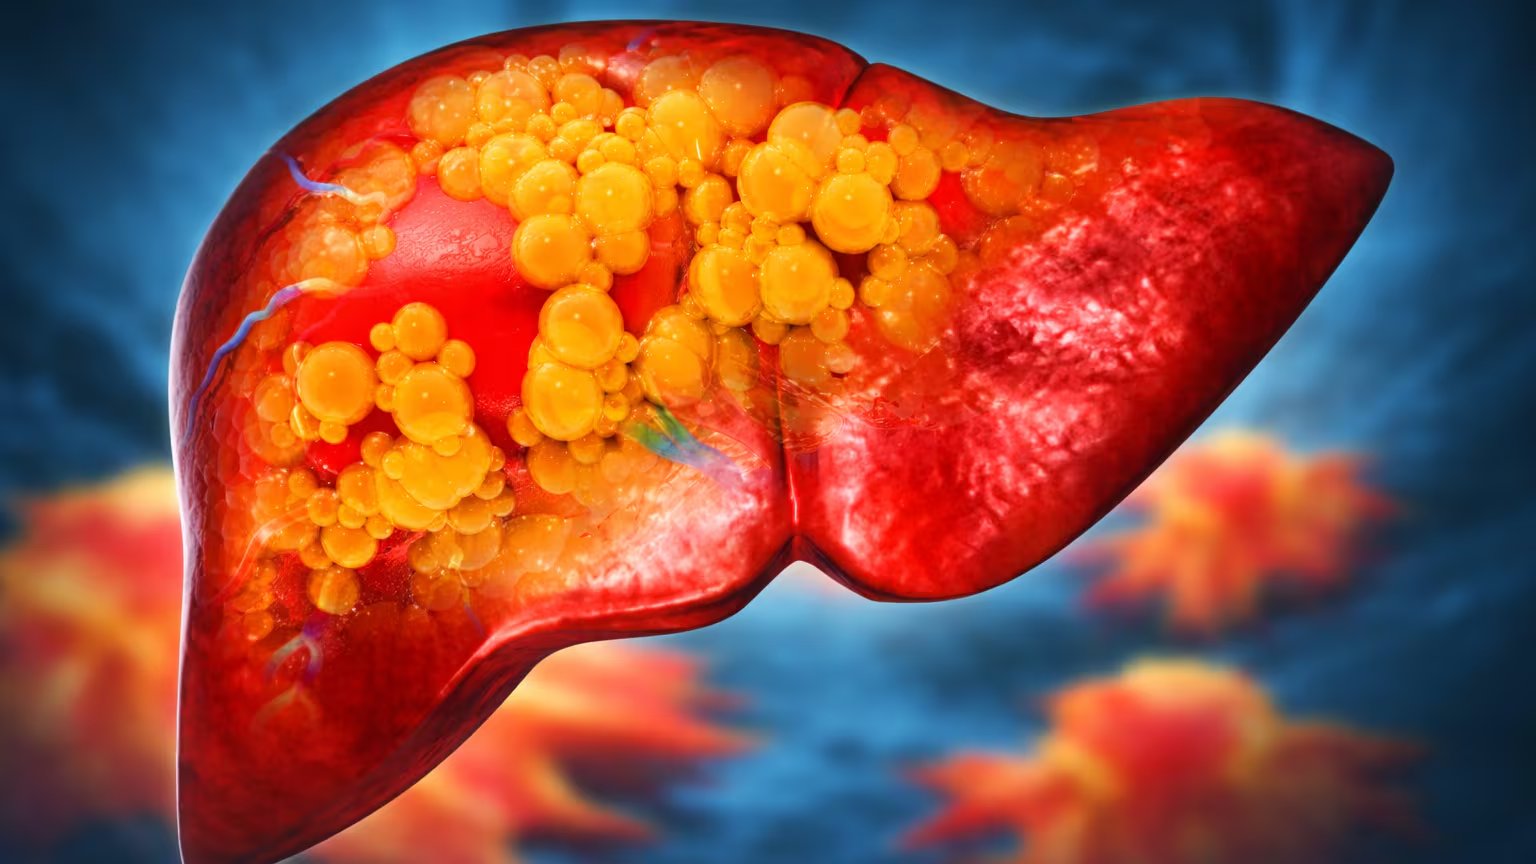

El desarrollo progresivo del hígado graso vinculado a la disfunción metabólica (MASLD) representa actualmente un reto mayúsculo para el bienestar público en América Latina. De acuerdo con estadísticas proporcionadas por Siemens Healthineers, aproximadamente el 44% de los habitantes en México padece esta condición. Esta patología suele avanzar sin presentar sintomatología evidente, lo que facilita su evolución hacia cuadros clínicos de extrema gravedad, tales como la fibrosis, la cirrosis o incluso el carcinoma hepático, si no se interviene de manera oportuna.

Esta afección no se limita a una simple acumulación lipídica; es el resultado de una compleja interacción de factores metabólicos. Entre los detonantes principales se encuentran una nutrición deficiente, el sedentarismo crónico y la predisposición genética de cada individuo. Cuando esta situación se agrava, sobreviene una etapa inflamatoria denominada MASH (esteatohepatitis vinculada a disfunción metabólica), la cual, de persistir, fomenta el desarrollo de fibrosis.

Actualmente, el nivel de fibrosis —definido como la cicatrización del tejido del órgano— constituye el indicador más relevante para predecir complicaciones fatales. Por esta razón, el reconocimiento temprano de este estadio es fundamental para definir el abordaje médico adecuado.